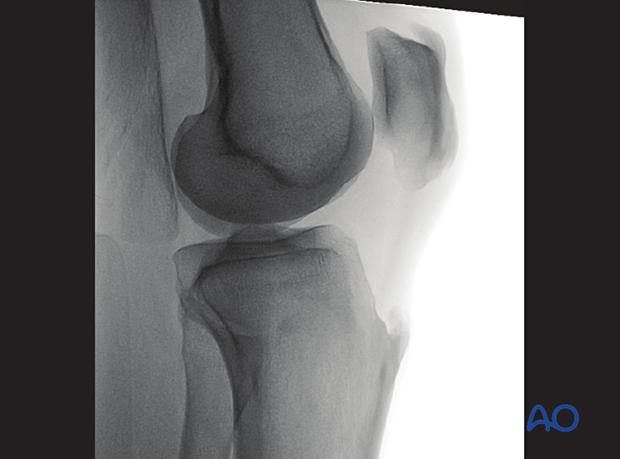

To obtain the optimal view, start from the optimal AP view and tilt the C-arm caudally until the AP view of the true tibial joint line is obtained (ca 10°).

The optimal view of the true tibial joint line is achieved when:

The following lines and landmarks can be seen:

This view is particularly useful to identify:

The correct angle between the tibial joint line and the tibial axis (85-90°).